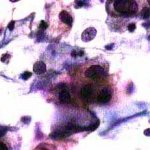

Δυσπλασίες τραχήλου μήτρας σοβαρού βαθμού (CIN III)

Ασυμπτωματική ασθενής 39 ετών. PH κόλπου 4,4. Κολποσκόπιση:

Στην δοκιμασία οξικού οξέως και στην δοκιμασία Lugol, αρνητική περιοχή, τόσο στο πρόσθιο, όσο και στο οπίσθιο χείλος του τραχήλου, σε ακτίνα 3-4 χιλ. και πλάτος περίπου 5 χιλ., με εικόνα διακριτικού επίπεδου μωσαϊκού.